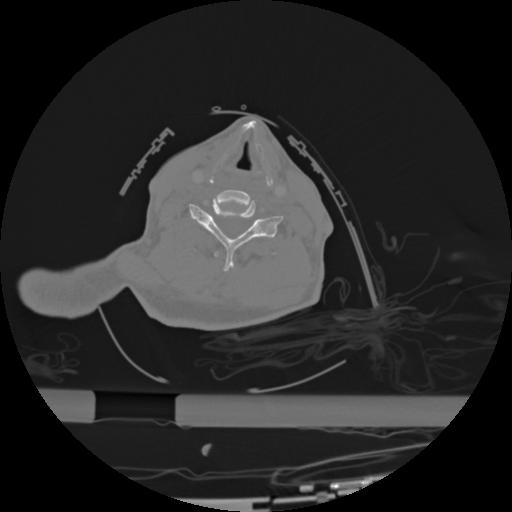

22 ANGIO,CE,Vol,0.5,ANGIO,,